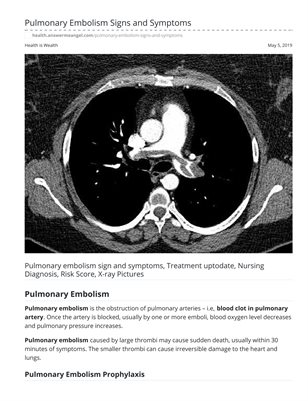

Pulmonary Embolism Signs and Symptoms

Pulmonary embolism is the obstruction of pulmonary arteries - i.e, blood clot in pulmonary artery. Once the artery is blocked, usually by one or more emboli, blood oxygen level decreases and pulmonary pressure increases. Pulmonary embolism caused by large thrombi may cause sudden death, usually within 30 minutes of symptoms. The smaller thrombi can cause irreversible damage to the heart and lungs.